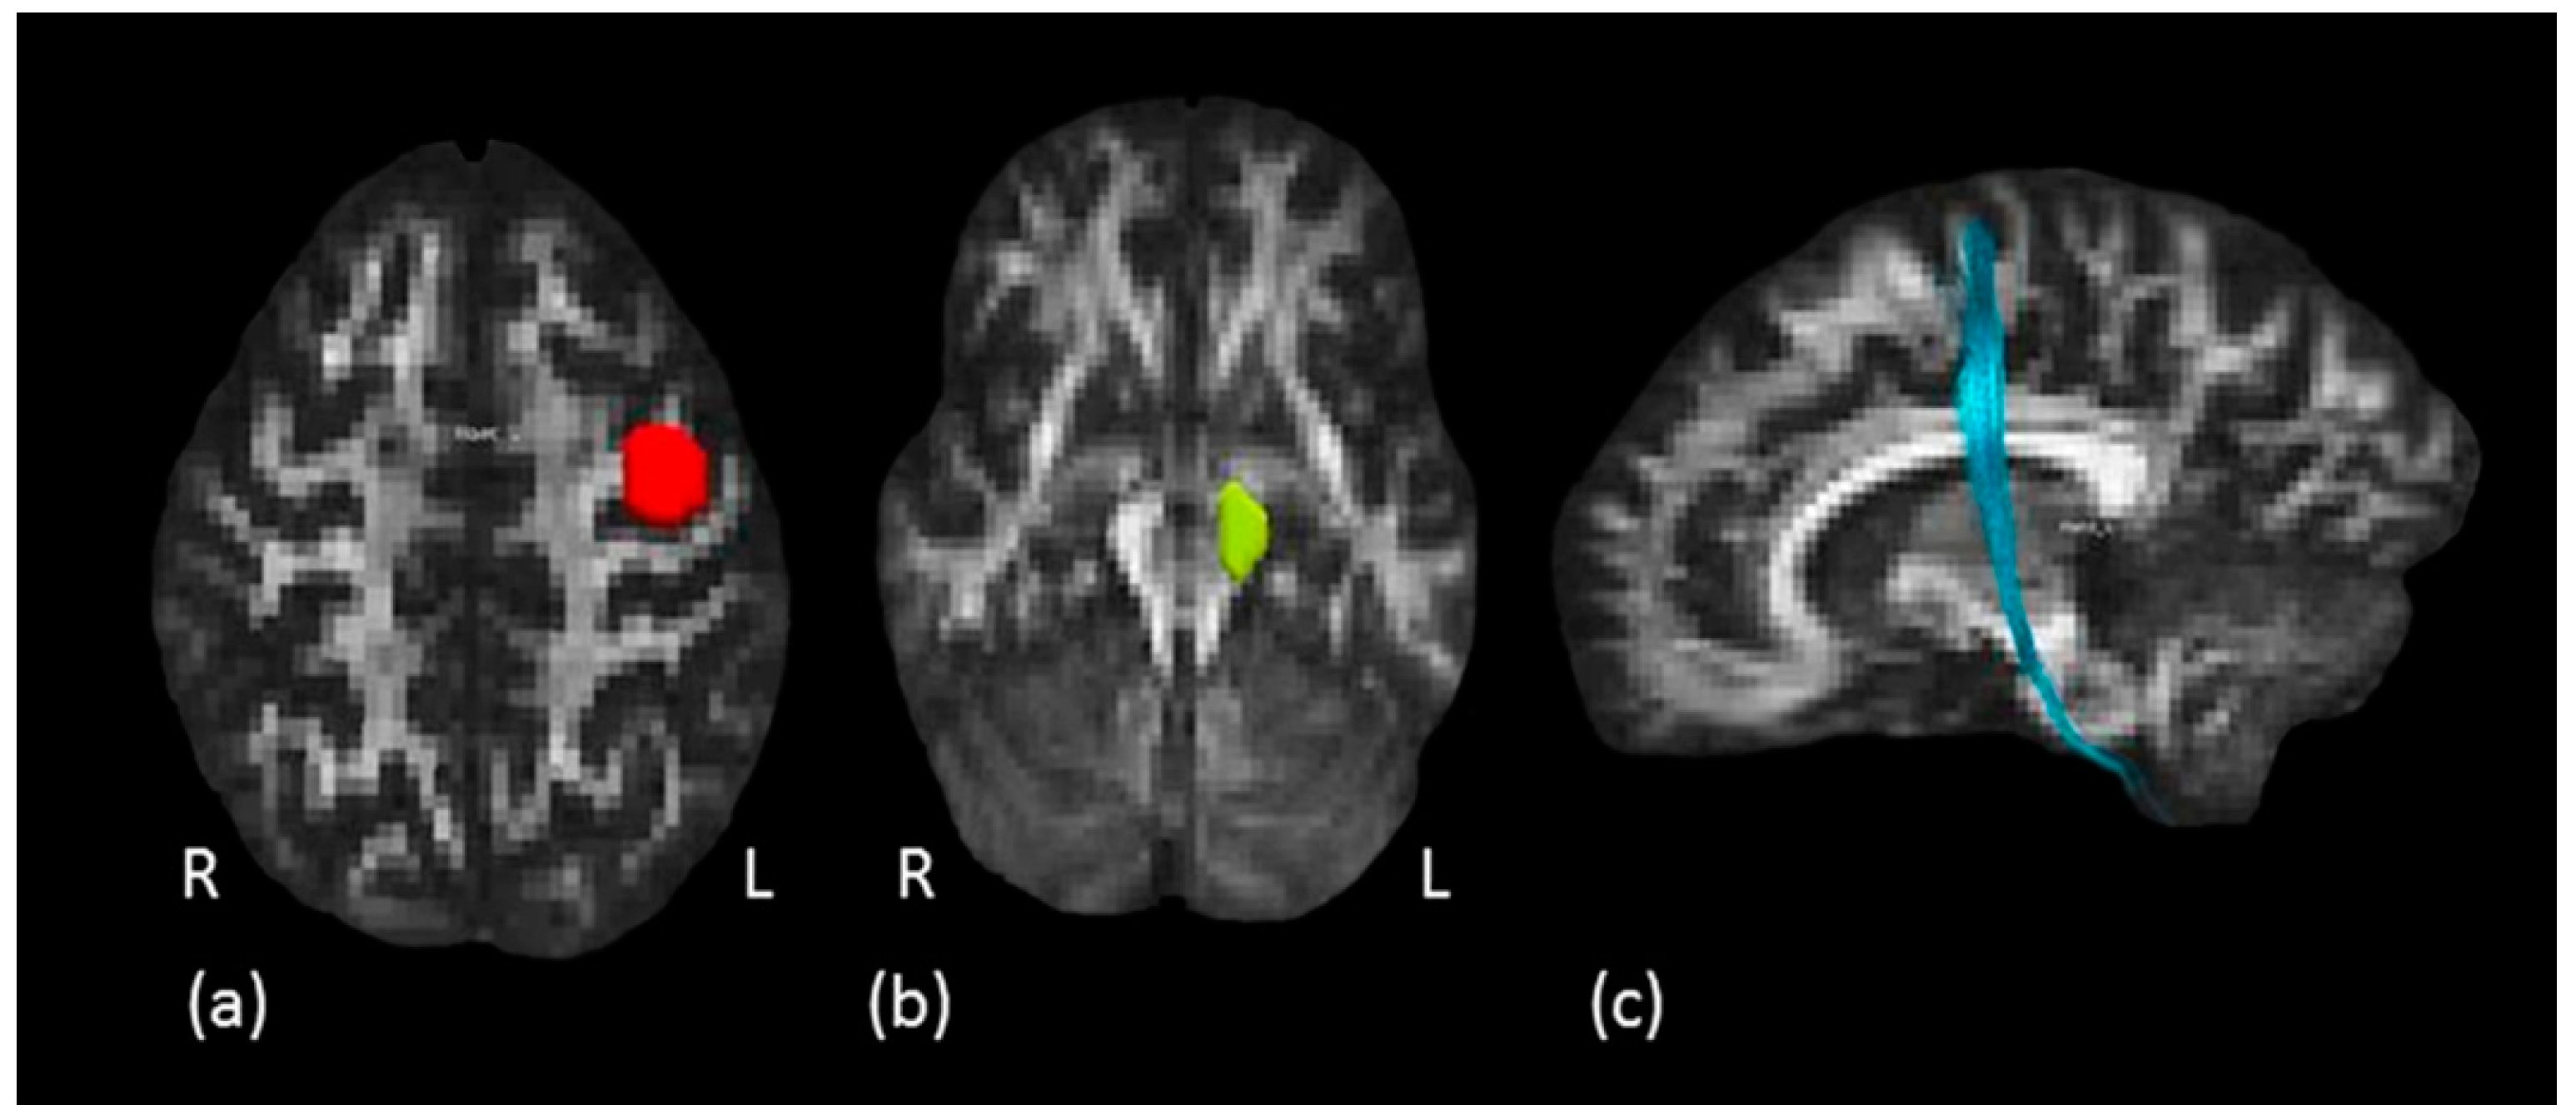

2.3.4. Tractography Dissections of the Internal Capsule, Corticospinal Tract and Hand Motor Tract